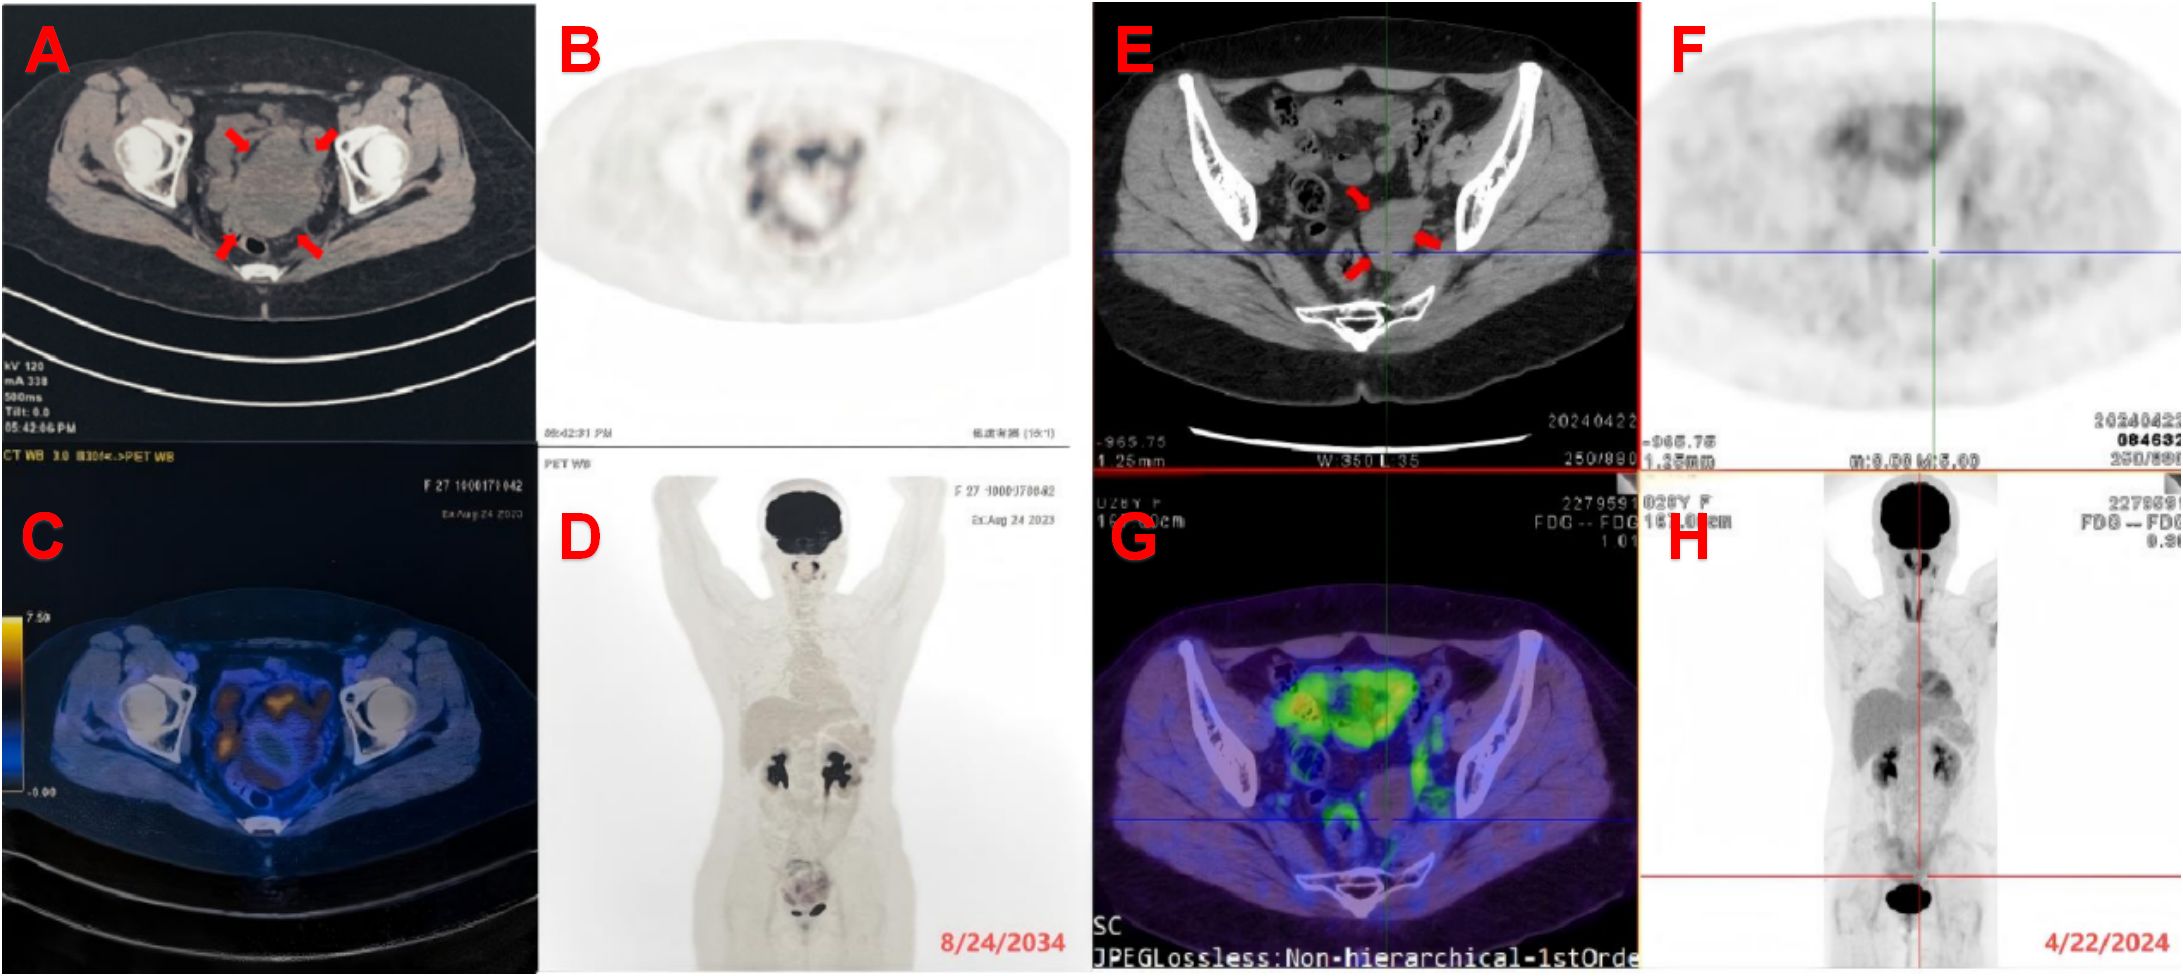

Background Surgery is the primary treatment for Endometrial Stromal Sarcoma (ESS), however, a substantial proportion of patients with ESS experience recurrence or metastasis. Currently, surgery and local ablation are the main treatments for recurrent ESS followed by chemotherapy, radiotherapy, immunotherapy, targeted therapy, and anti-estrogen therapy. Surgery and local ablation are invasive treatments and may carry risks such as intestinal damage and the risk of massive bleeding from tumor rupture. For patients who refuse or are unable to undergo surgery and local ablation, conservative treatment is not effective, and there is currently no definitive effective non-invasive or combined treatment plan. Case presentation This report presents a case of a patient with recurrent endometrial stromal sarcoma who refused surgical and local ablation treatments. After receiving HIFU treatment combined with chemotherapy, the progression of the tumor was effectively inhibited, the tumor volume significantly reduced, and liver function was restored during the HIFU period, providing an opportunity for chemotherapy. Conclusions HIFU combined with chemotherapy may provide a new treatment strategy for patients with recurrent, metastatic endometrial stromal sarcoma, or those who are unsuitable for surgery, local ablation, or those with poor baseline status unable to tolerate intensive chemotherapy.